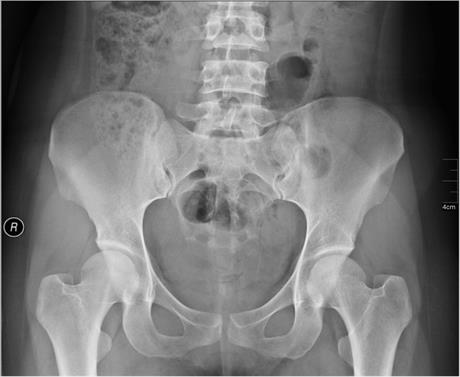

Frka zbog slike

Raspitivanje u bližoj i daljoj, te najčešće nestručnoj okolini, kao i pretraživanje interneta neće pomoći u postavljanju dijagnoze